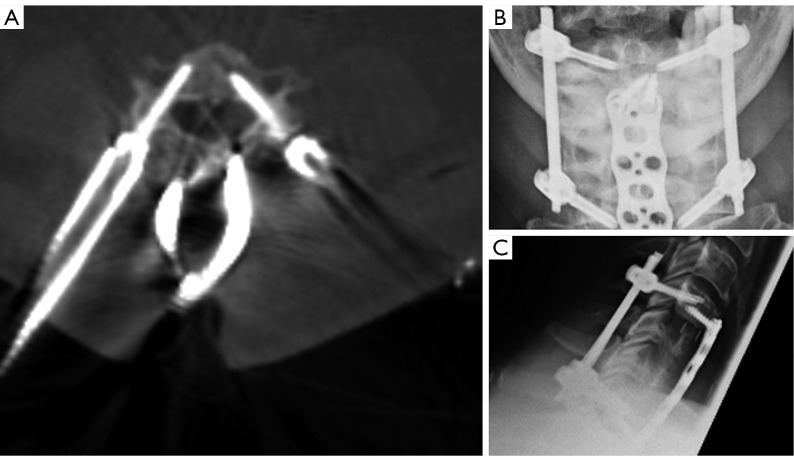

Methods: Between January and July 2023, we treated a cohort of ten patients using a new cervical MIS platform. Forty pedicle screws were inserted percutaneously in the c-spine using intra-operative computed tomography (CT) guided navigation and retrospectively analysed for accuracy using a modified Gertzbein & Robbins (G&R) classification. Adverse events and other patient-related data were also documented.

Results: Ninety percent of all screws were placed accurately (80% on perfect trajectory, 10% showed minor perforations). Another 10% (four screws) caused pedicle wall breaches between 2 and 4 mm, but were not revised, since misplacement was not associated with neurological deficit or inferior biomechanics. One patient experienced neurological deterioration, but not associated with screw misplacement. The transverse foramen was breached twice, however not endangering the vertebral arteries.